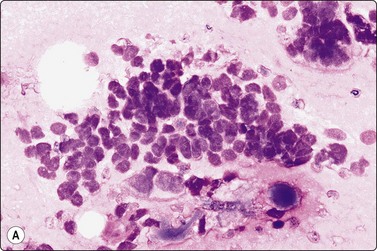

Nasopharyngeal carcinoma (NPC) (Figs 4.8, 4.9, and 5.59)44-47

image

Fig. 4.8 Nasopharyngeal carcinoma (squamous cell carcinoma, WHO type II)

Epithelial fragment of spindly and basaloid squamous epithelial cells with no evidence of keratinization (Pap, HP).

image image

Fig. 4.9 Nasopharyngeal carcinoma (undifferentiated, lymphoepithelial type, WHO type III)

Loose clusters of undifferentiated epithelial cells with vesicular nuclei, prominent nucleoli and pale fragile cytoplasm. Background of lymphocytes. (A, MGG, HP; B, H&E, HP).

Criteria for diagnosis (undifferentiated carcinoma nasopharyngeal type (UCNT)/WHO type III/lymphoepithelial carcinoma)

Undifferentiated malignant cells, single and in clusters,

Variable amount of pale, fragile cytoplasm,

Large vesicular nuclei with prominent central nucleoli,

Admixture with, and background of, lymphoid cells, often with prominent plasma cells,

Ancillary tests: neoplastic cells positive for cytokeratin, negative for lymphocyte markers. EBV-associated nuclear antigen.

Nasopharyngeal carcinoma (NPC) is a clinicopathologic entity different from other squamous cell carcinomata of the head and neck. It is distinguished by its particular histology, geographic distribution, relationship to Epstein-Barr virus, and the absence of an alcohol or tobacco etiological relationship. A proportion of NPCs show squamous differentiation and the cytological pattern of non-keratinizing squamous cell carcinoma (squamous cell carcinoma/WHO type II) (Fig. 4.8). Keratinized cells (WHO type I) are uncommonly found. The majority of NPC are poorly differentiated or undifferentiated. Cells from undifferentiated NPC (UCNT, WHO type III) form loose clusters with no specific microarchitectural pattern, and are usually mixed with lymphoid cells. In the ‘lymphoepitheliomatous’ type (Schmincke-Regaud) the cells tend to be less cohesive, resembling Hodgkin’s disease or large cell non-Hodgkin lymphoma. However, in NPC, the malignant cells are still clustered and have more abundant pale cytoplasm contrasting with the lymphoid cells in the background (Fig. 4.9). Plasma cells are frequently found among the lymphoid cells. Immunostaining for cytokeratin and a pan-lymphocyte marker is helpful. Epstein-Barr virus-associated nuclear antigen is demonstrable by anticomplement immunofluorescence in undifferentiated tumors. Other patterns of growth may occur and may cause diagnostic problems; for example, spindle cell forms may be difficult to recognize as carcinoma.

NPC frequently presents to the cytologist as a lymph node metastasis in the neck without a known primary. Cytological recognition is important since the primary is often clinically occult.